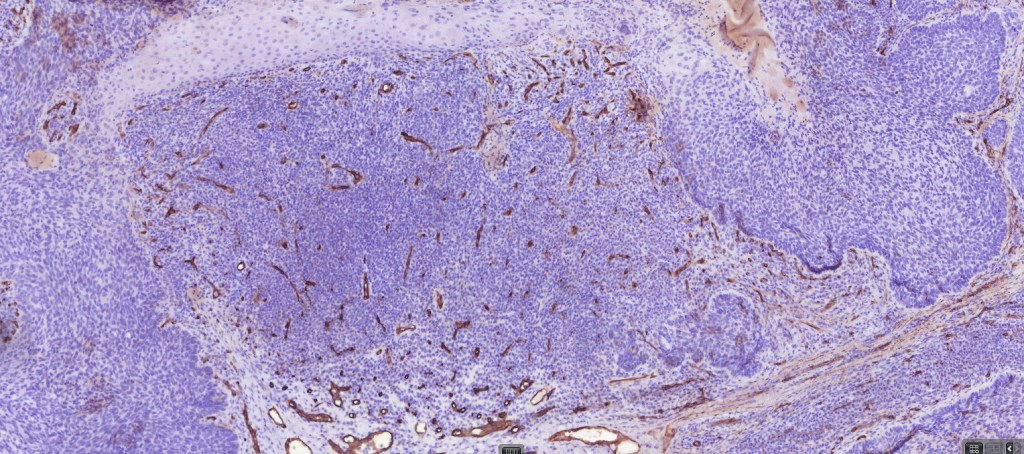

•Both epithelial & fibrous stromal components

•AE1/AE3, BerEP4, p53, p63, androgen receptor, CD10 (epithelial, negative in stroma)

.EMA, CEA, CD34-ve